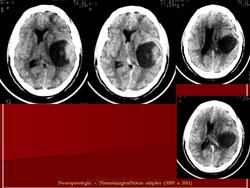

ГМ. Примитивная нейроэктодермальная опухоль (ПНЭО). +

Примитивная нейроэктодермальная опухоль (ПНЭО)